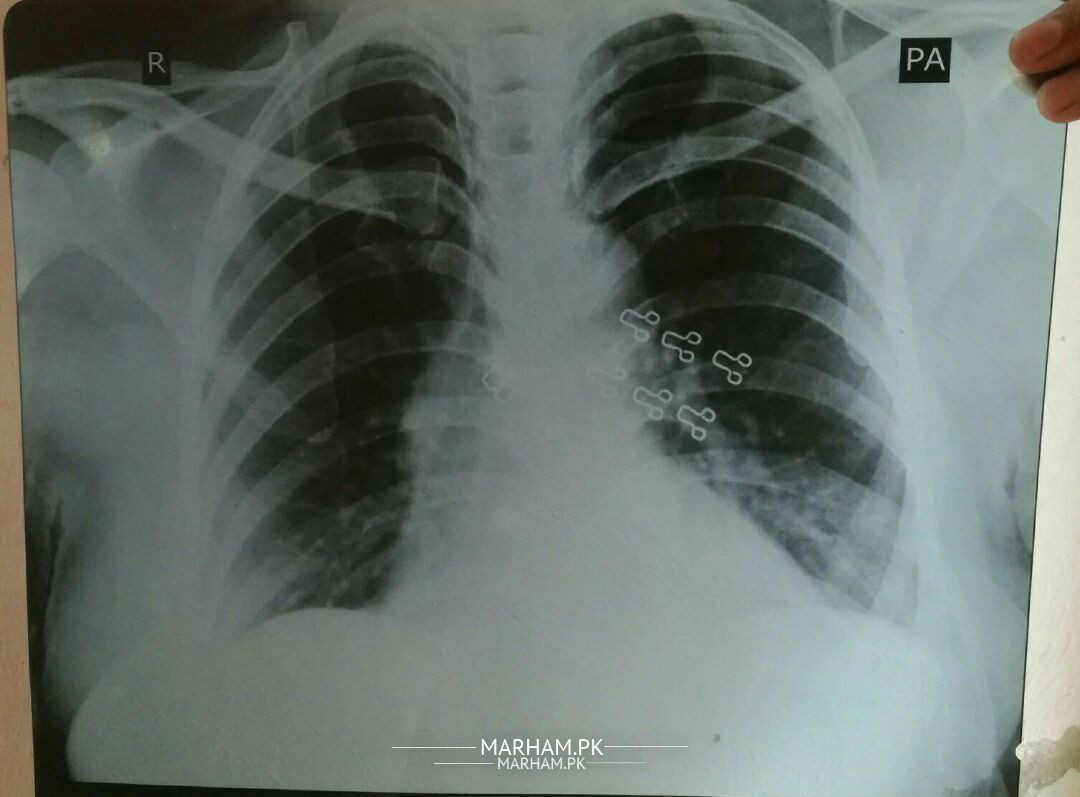

Assalam-O-Alaikum respected Doctors (Pulmonologist) please read this attached X- ray and tell us no worries , precautions and suggestions. Thanks in advance for your precious time

#Past history about Ami jan 5,6 years phle fiver hwa tha or English medicines react kr gye thn side effect ya inform kea tha CMH waln ne ca breathing drains narrow h gye h or saath ma work krne pa heart beat speed increase h jte the tb leave kr dn thn or sb thk h gya tha or tb se ab tak mostly homeopathic medicine use krtn h dosre hard h kafi.

(*_*) Current situation of Ami jan Achanak 6 years later or 2,3 months phle Ami ki tabiyat kharab hwe h Ami g ca breathing process ma problem h not Everytime however twice or 3 times a week mostly night ma hta or saath ma khushq khanci bhe lene se fori aram a jta h for some hours , doctor's co check kraya sb ne yahi kaha sb thk h preshni ki bat ni h but ma bhttt preshn h Ami ca lea ALLAH pak Ami g co sehatyab farmyn Ameen.

what's spo2 level

Ap ki history (mareez ki bemari ki tafseel) sy youn lag raha hy k umeid hy ziada preshani ki bat nhi. Lekin apni ami ko Nezdeek pulmonologist ko dekha dain. kion k check up hojana behtar rahy ga.

Umeid hy Dr ki dawai buri nhi lagy gi. ap Dr sy khul k bat karain apny ami ki bemari k bary mai...

sirf x ray kafi nhi pori maloomat k lei.